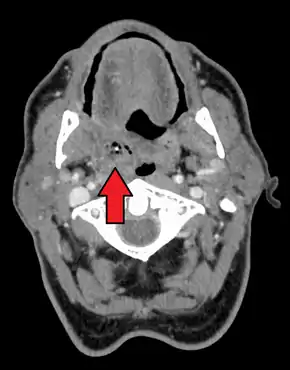

| Right sided peritonsillar abscess | |

Diagnosis is usually based on the symptoms.[1] Medical imaging may be done to rule out complications.[1] Medical imaging may include CT scan, MRI, or ultrasound is also useful in diagnosis.[1]